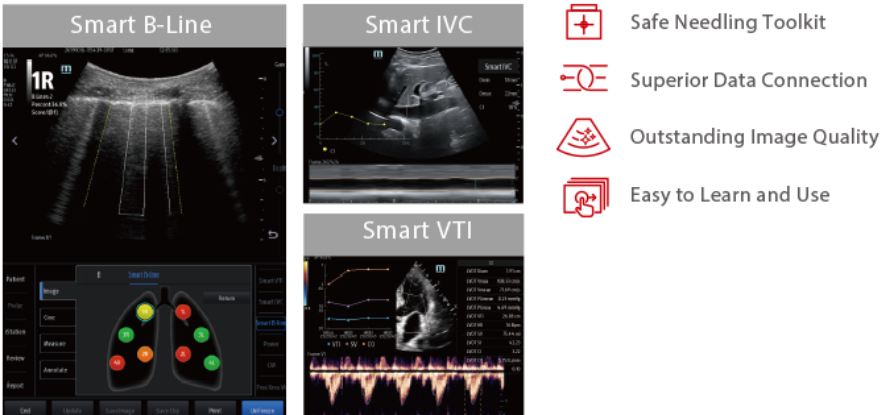

Smart Fluid Management